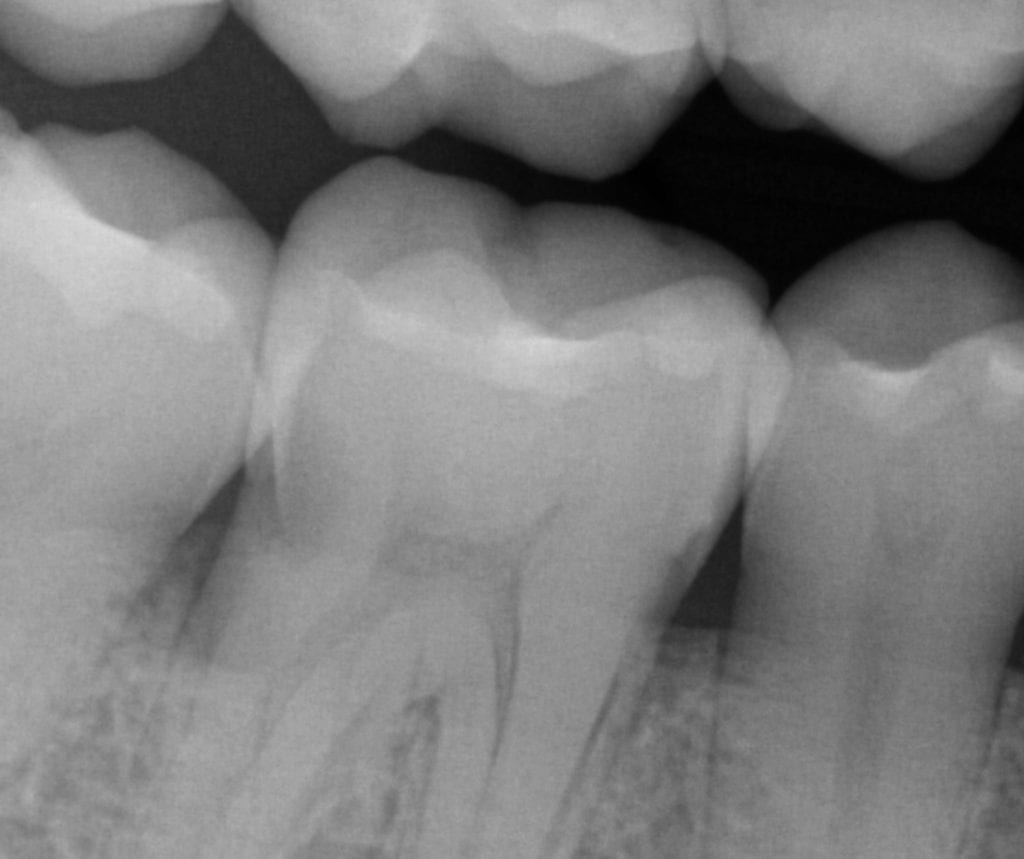

Radiograph taken after a week following insertion of the PFM crown Zirconia Crown In Xray Studies that assessed the performance of zirconia crowns for primary teeth using outcomes such as gingival and periodontal health, parental satisfaction, color stability,. To determine the mean and maximum reduction. Zirconia crowns offer a number of advantages, including durability. The included studies reported that zirconia crowns for primary teeth were associated with better gingival and periodontal health, good. The monolithic. Zirconia Crown In Xray.